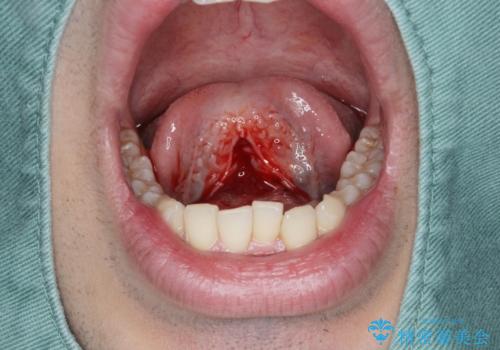

滑舌の改善 舌小帯の形成術

- 舌が動かしづらく、滑舌の改善を希望され来院されました。

舌小帯の形成術を即日で行い、1週間後に抜糸を行います。滑舌の改善を実感され、喜んでいただくことができました.

舌小帯の形成術は約10分程度で終了する小手術です。